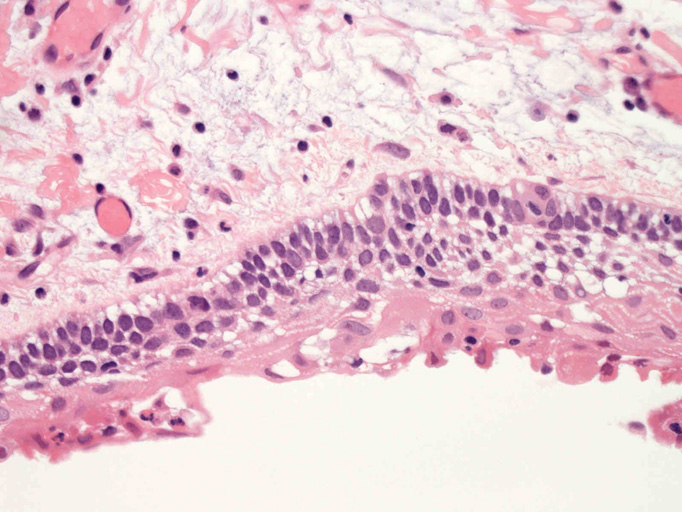

嚢胞性病変の壁を裏装する上皮はspongiosisあるいはintraepithelial edemaと棘細胞への分化を示す。7-15層の上皮で, 基底細胞はpalisadingを呈している。上皮脚は平坦で角化は認められない(Fig.01-Fig.04)。嚢胞壁はわずかにmyxoidな成分を伴うdensな膠原線維性間質からなり, その中に小さな胞巣状の歯原性上皮巣が散在している。核分裂像は認められない(Fig.05, 06)。

病理組織診断:unicystic ameloblastoma, luminal subtype